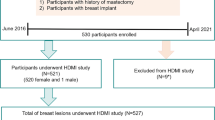

This prospective study was approved by our institutional review board (IRB#: 12–003,329 and IRB#: 19–003,028) and was Health Insurance Portability and Accountability Act-compliant. From June 1, 2016 through April 1, 2021, 538 participants with suspicious ultrasound-identified breast lesions and with recommendation for biopsy were recruited for this study. As expected, most cases were classified as BI-RADS 4 and 5; however, three of BI-RADS 3 patients included in this study underwent the biopsy due to patient preference. Volunteers with breast implants or prior mastectomy were excluded during recruitment. Among them, participants who underwent a SWE study only or HDMI study only were excluded from this study. Finally, 508 participants (mean age, 54 years ± 15), including 507 female participants and 1 male participant, with 514 suspicious breast lesions were included in this study. A flowchart for the participant exclusions is shown in Fig. 1. A signed written IRB-approved informed consent with permission for publication was obtained from each enrolled participant prior the study. For all the participants, the pathology results from biopsies served as the reference gold standard and both the SWE study and HDMI study were conducted prior to the biopsy.

Flowchart for the participants. *19 participants were excluded from the SWE study because the SWE study was cancelled due to insufficient time before biopsy. **11 participants were excluded from the HDMI study (1 was excluded because the scanned lesion was not biopsied, 10 were excluded because of technical problems with the system). HDMI: high-definition microvasculature imaging. SWE: shear wave elastography